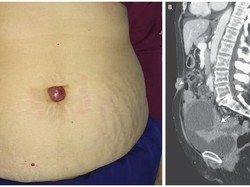

Para peneliti melaporkan perkembangan terbaru terapi pengobatan kanker stadium lanjut. Terapi ini memodifikasi sel imun penyintas kanker.